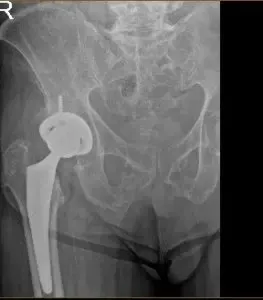

Radiografía de un reemplazo de cadera

Las imágenes postoperatorias muestran artroplastia total de cadera derecha, en buena alineación, cambios degenerativos sacroilíacos leves. El paciente volvió para una cita postoperatoria para la extracción de la grapa y el pronóstico es bueno, gracias a una cirugía sencilla. El paciente cumple con el programa de fisioterapia ambulatoria y soporta peso completamente bilateralmente.